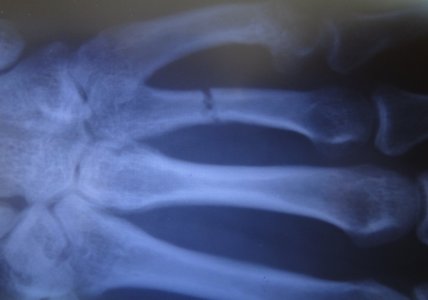

Сказал ходить 5 недель + кальцемин 2 р. в день и контрольный снимок через 7 дней, вот он:

После этого я отходил 5 недель со дня репозиции, сняли лонгету, и сделали снимок: